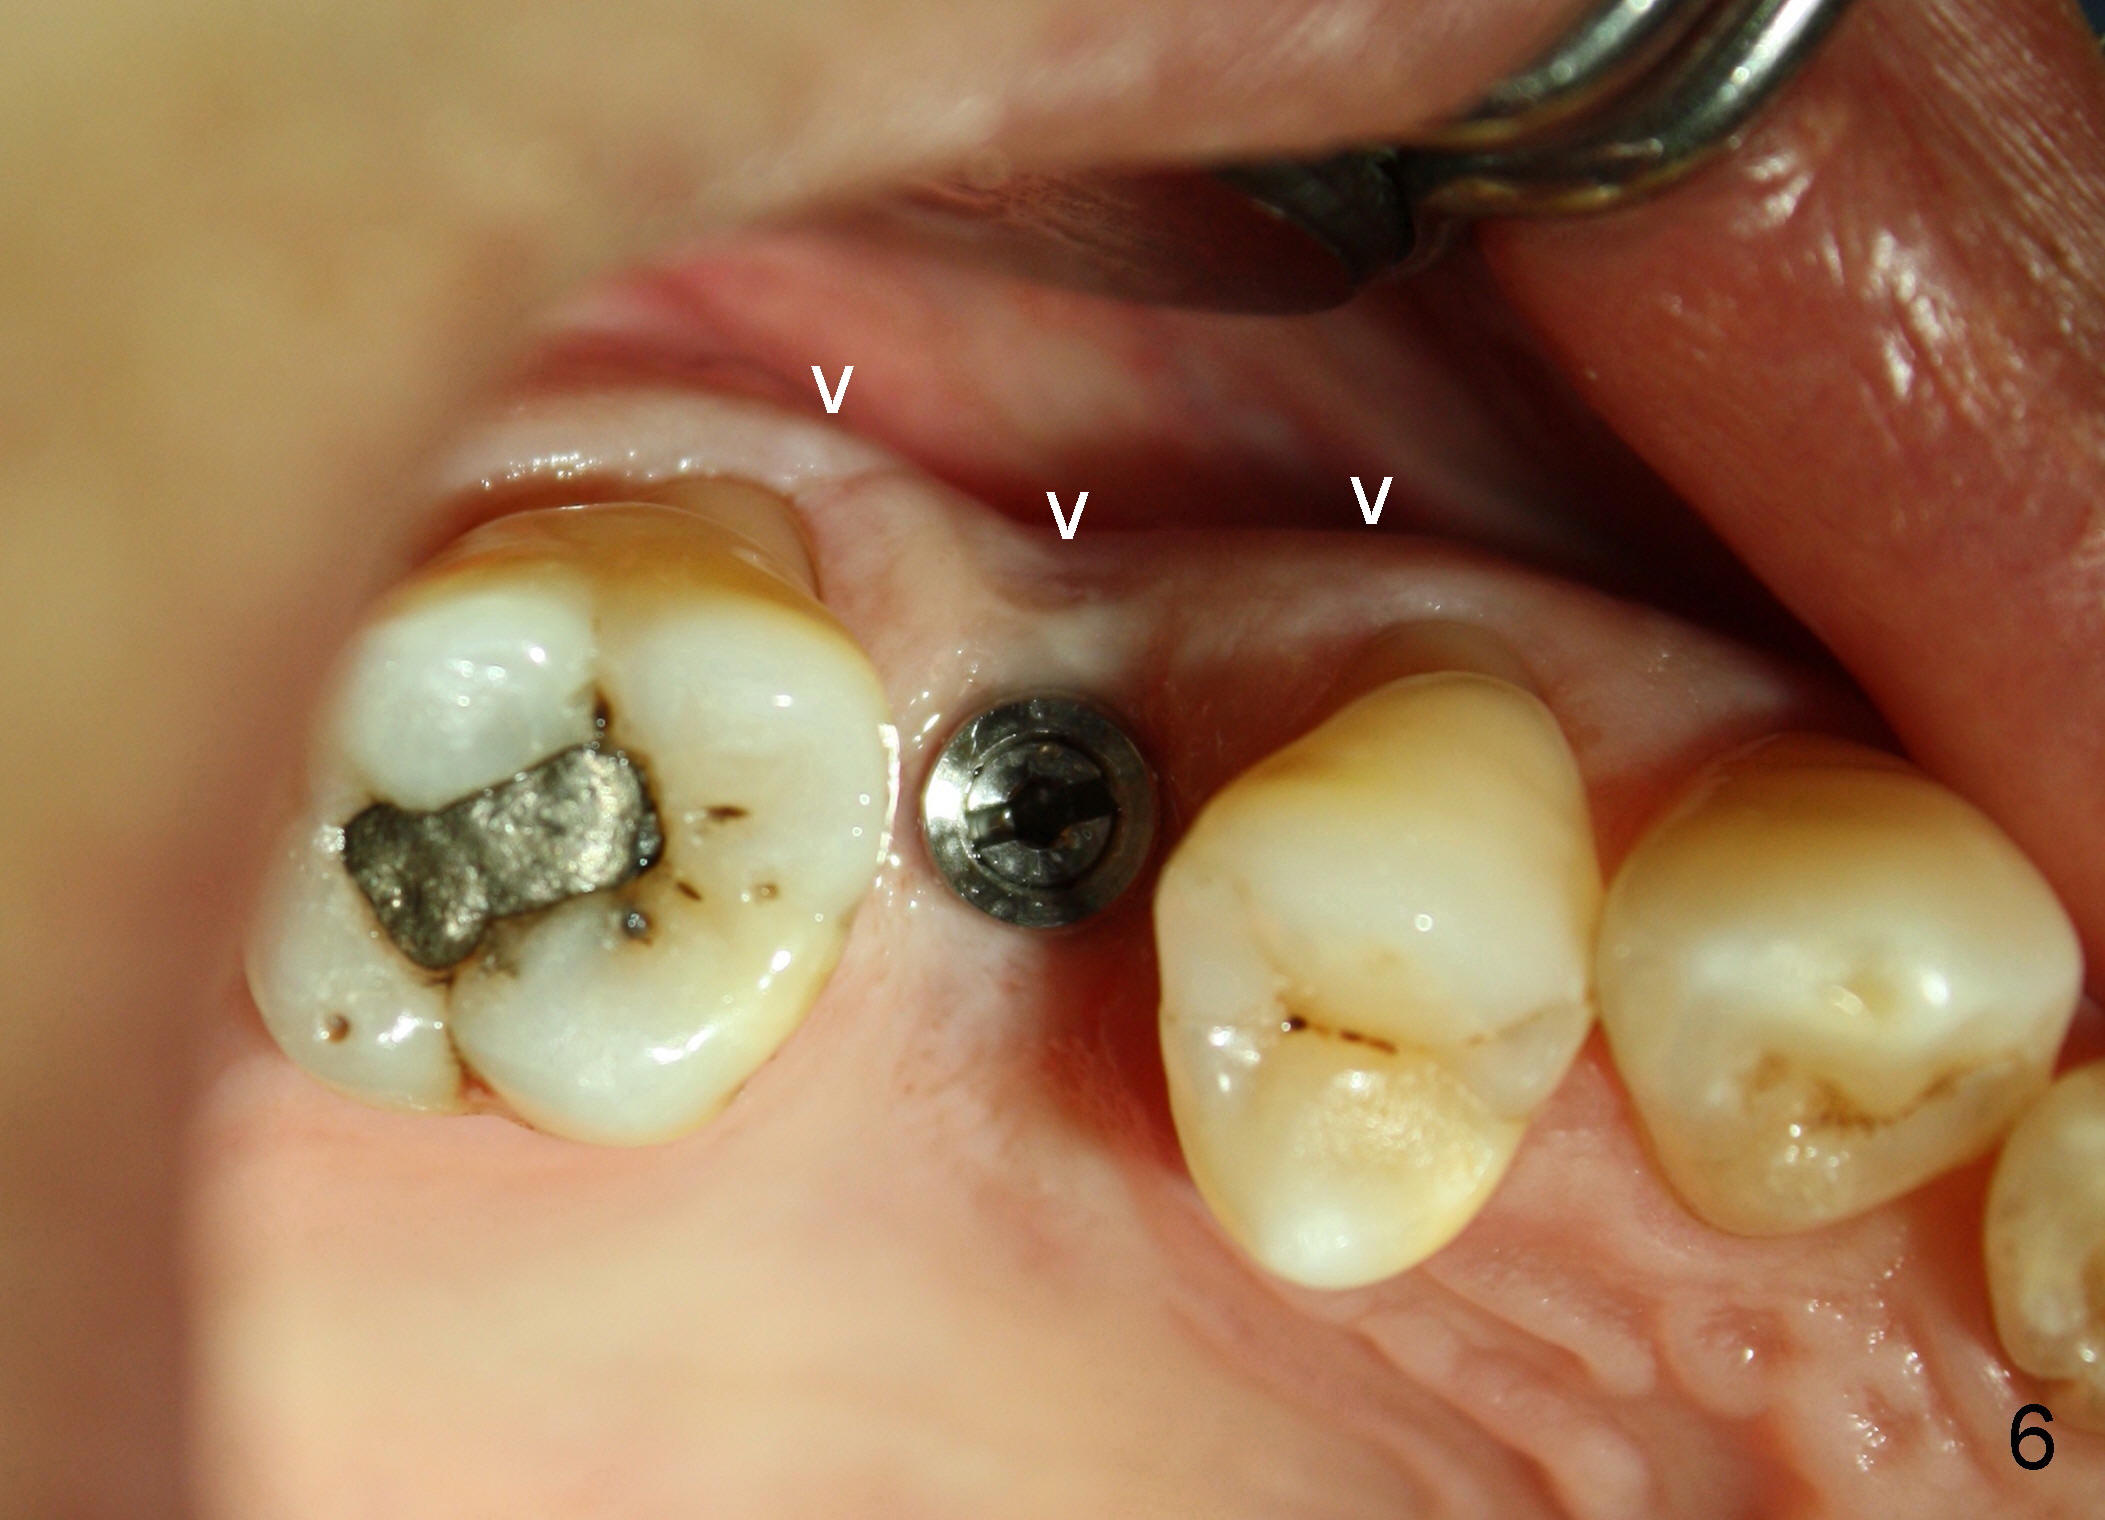

The tooth #4 was removed from a 41-year-old man (Fig.1). Fig.2 was taken 1 year and 7 months post extraction. Osteotomes (Fig.3,4) were used to create osteotomy (7 yr 9 m post ext). A 4x14 mm implant was placed below the sinus floor with insertion torque > 60 Ncm (Fig.5). The surgery was flapless (Fig.6). No antibiotic was taken pre- and post-op. The implant was found to be tender and loose. It was removed without bone graft.